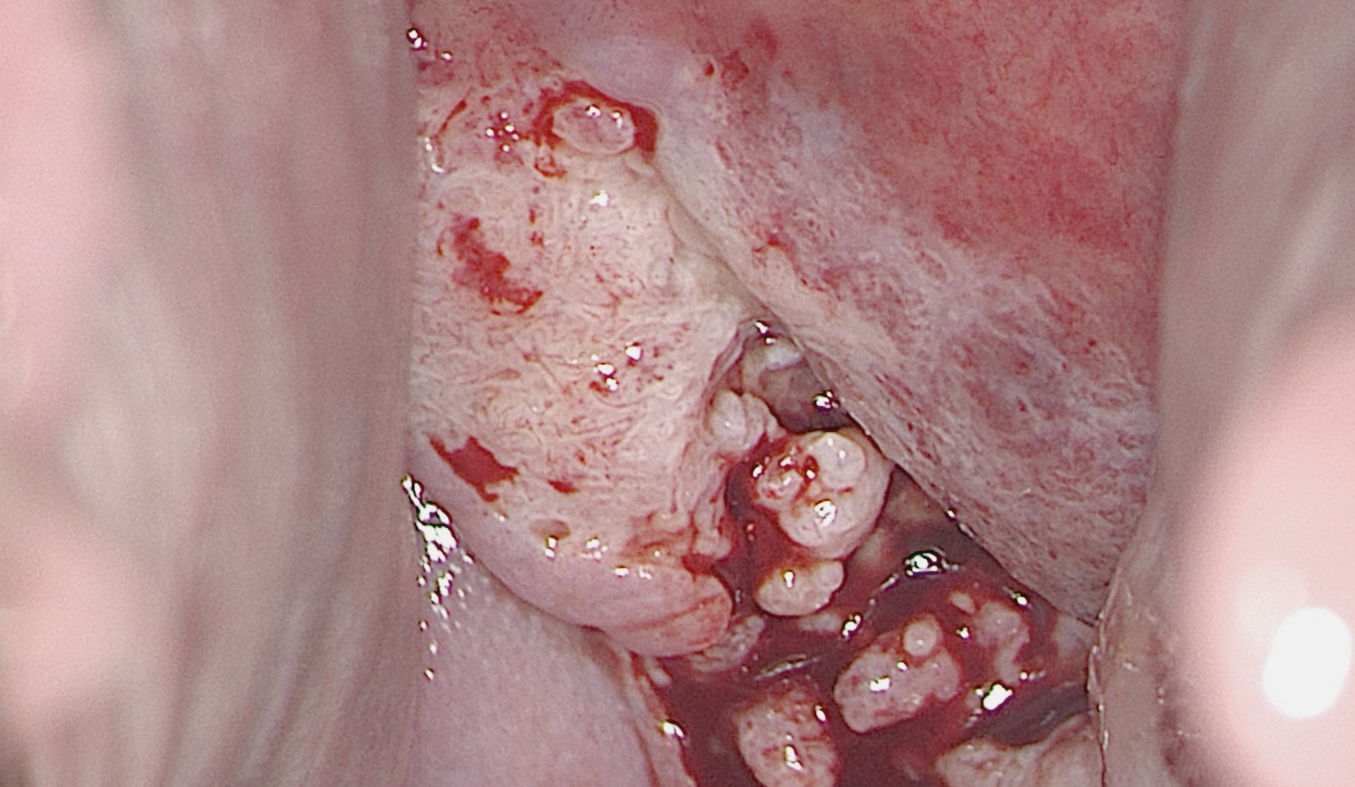

Atypical transformation zone type 2 with ulceration, bleeding and atypical vessels, suspicious for cancer.